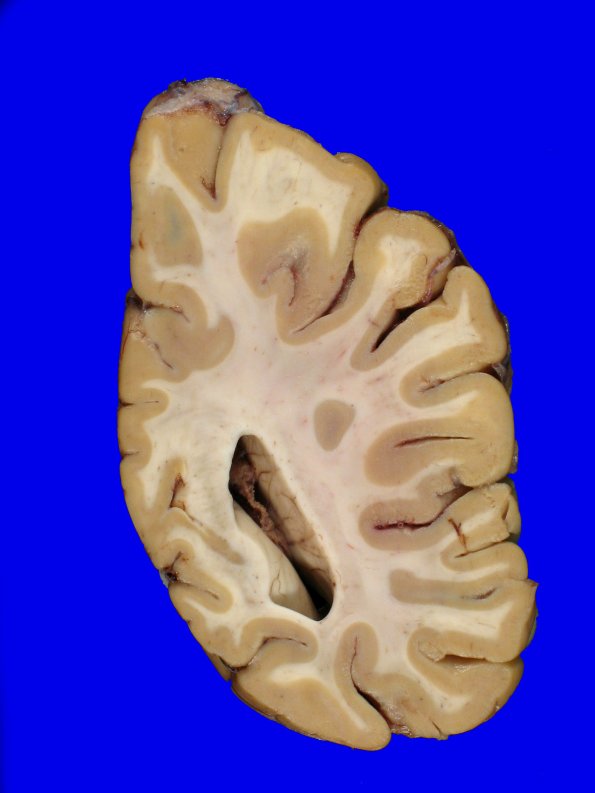

10B2 NCL (Case 10) Gross_21

There was mild generalized atrophy of the cerebral hemispheres and mild dilatation of the lateral ventricles.